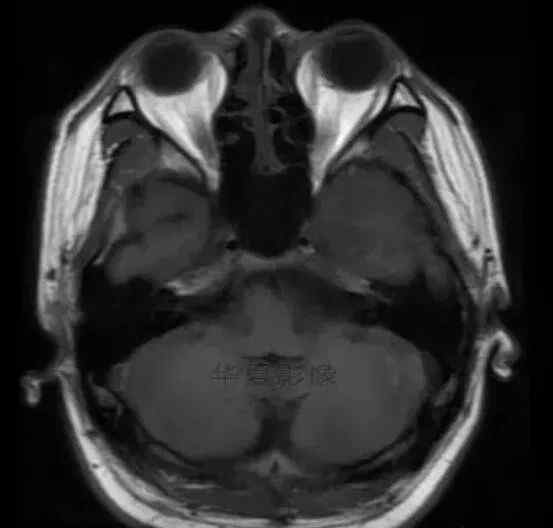

1.左侧颞叶、海马和岛叶T1WI信号低,T2WI信号高

2.病变没有明显的边界

3.占用效果不明显